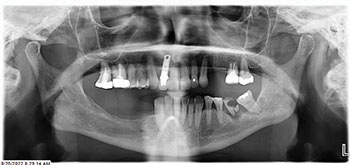

Our patient, a healthy woman in her early 60s, presented with a terminal dentition (Fig. 1) in both arches, collapsed bite, unstable occlusion, midline shift, asymmetric horizontal plane and bone loss (Fig. 2). She was looking for a fixed solution that would give her the confidence to smile, eat and socialize without restrictions. Several previous treatment plans suggested placing provisional dentures as an interim until the implant stabilized, which did not resonate with her desires during the healing phase.

Fig. 1

Fig. 2

Surgery was uneventful. Extractions, site preparations and implant placements went according to plan (Fig. 3). In the maxilla, we placed six implants following the “All-on-6” concept, ensuring posterior spread for optimal load distribution. Six implants were also placed in the mandible following a similar approach.

All implants achieved excellent primary stability (>35 Ncm Torque and ISQ values averaging 72 to75), which allowed us to proceed with immediate loading (Fig. 4). Using SprintRay 3D printed provisionals in OnX Tough 2 resin, we delivered fixed temporaries the next day post-surgery (Figs. 5–8).